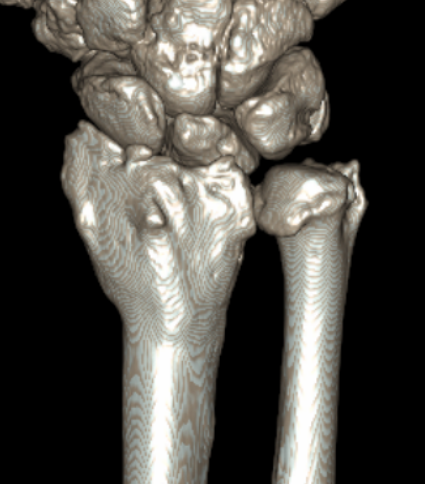

CT

CT guided 3D planning

- RCT of 40 patients with radial malunion

- 2D versus 3D planning and patient specific surgical guides

- 3 degree better correction in 3D group

- non significant trend towards better outcomes in 3D group

Intra-articular osteotomy

Indication

Step deformity

No radiocarpal osteoarthritis

Technique

Dorsal 3/4 approach and open radiocarpal joint